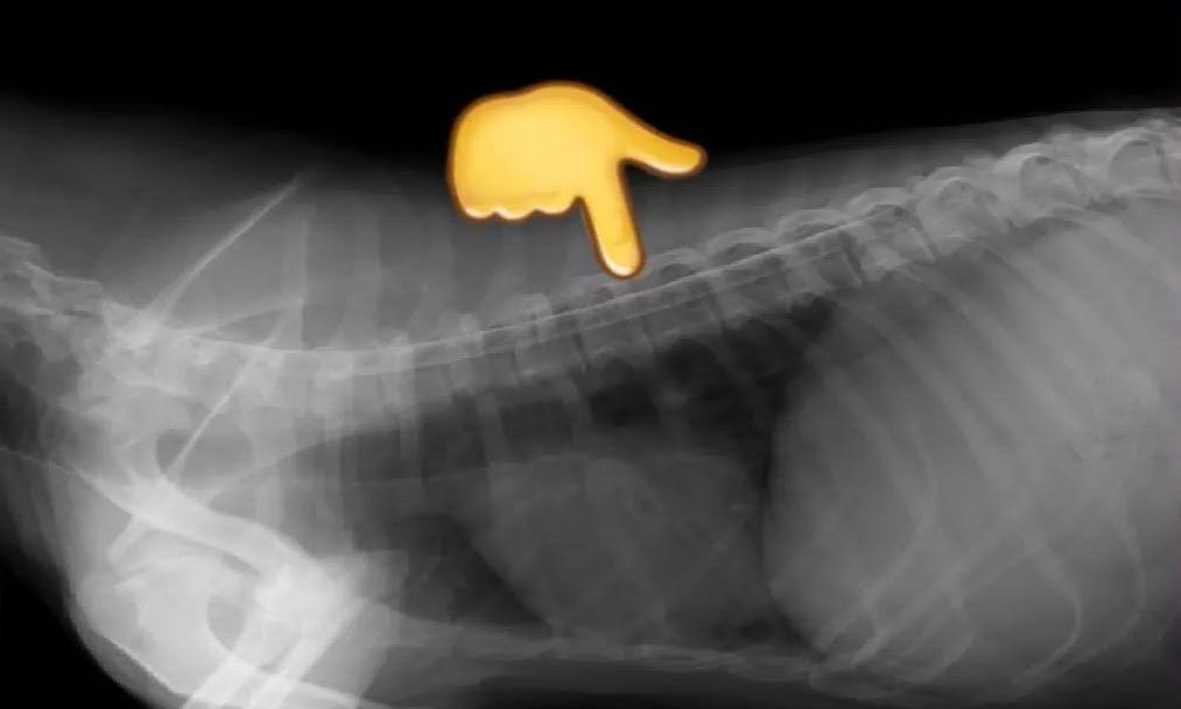

Diagnóstico por Imágenes

Radiografías Digitales, de contraste y simples, mielografías, ecografías.